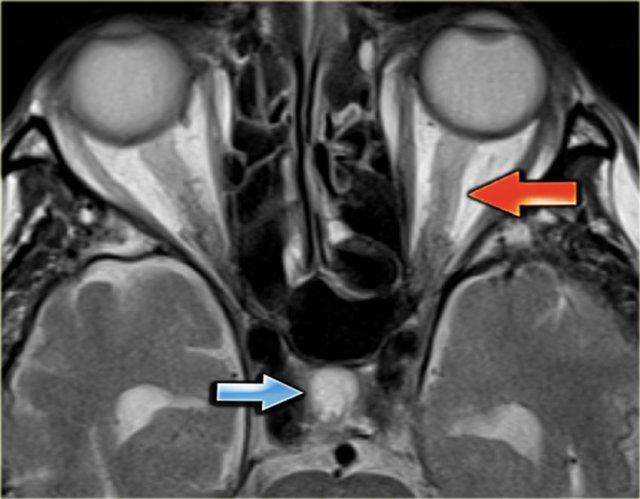

Hình ảnh bên trái là chuỗi xung T2W với tín hiệu trống dòng chảy bình thường ở xoang sigma phải và tĩnh mạch cảnh trong phải (mũi tên xanh dương).

Bên trái có tín hiệu cao bất thường là kết quả của huyết khối (mũi tên đỏ).